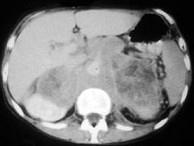

问题 男,76岁,全身浅表淋巴结肿大,请结合下列图片作出诊断()

选项 A.肾上腺腺瘤 B.肾上腺癌 C.肾上腺嗜铬细胞瘤 D.肾上腺转移瘤 E.肾上腺淋巴瘤

答案 E